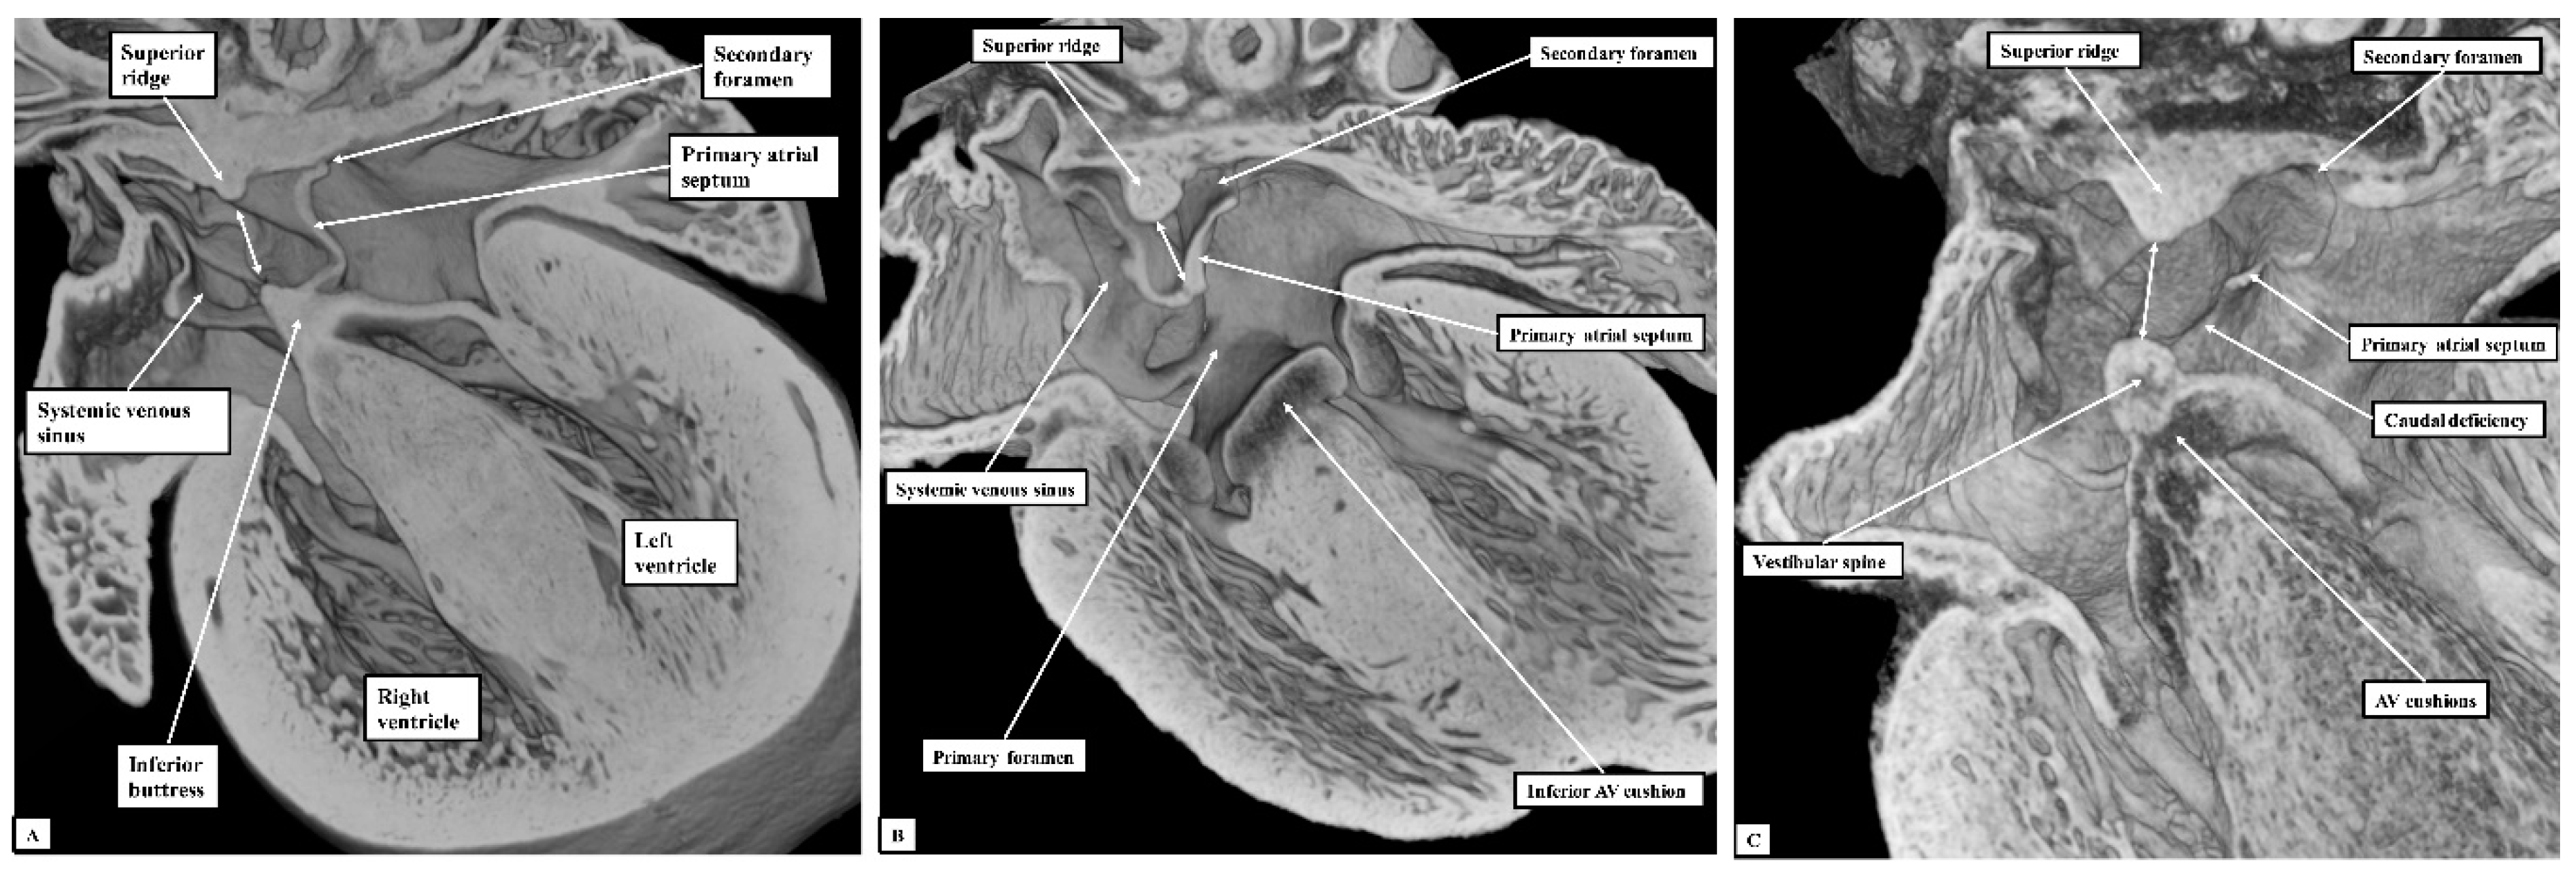

Figure 5. The images show ventral (Panel A) and more dorsal (Panel B) sections taken from the same episcopic dataset prepared from a developing mouse embryo sacrificed on the eleventh day of intrauterine development (E10.5). The lower panels show similar four-chamber sections at the stages of embryonic days 11.5 (Panel C) and 13.5 (Panel D) Abbreviation: AV—Atrioventricular.

At E10.5, the primary atrial septum can be recognised as a muscular ridge growing from the roof of the atrial component of the heart tube, which is a common structure at this stage of development. By this stage, the borders of the confluence of the systemic venous tributaries with the common atrial cavity are already marked by the venous valves, with the opening of the systemic venous sinus already committed to the right side of the developing atrial chamber (Figure 5A). The atrioventricular canal at this early stage is committed exclusively to the cavity of the developing left ventricle, although the parietal wall of the right atrium is already in continuity with the wall of the developing right ventricle in the roof of the embryonic interventricular communication. The primary septum itself carries a mesenchymal cap on its leading edge, with the space between the cap and the atrioventricular cushions representing the primary atrial foramen. Dorsally at this stage, the atrial walls are continuous with the pharyngeal mesenchyme through the persisting mesocardial connection. Growth from the mesenchyme into the right margin of the mesocardium has already produced inequality in size of its rims, which now protrude into the atrial cavity as the pulmonary ridges (Figure 5B). As yet, there is no formation of the pulmonary veins, but the floor of the dorsal mesocardial connection, known as the pulmonary pit, will eventually provide the site of connection between the developing pulmonary veins and the atrial cavity.

By the next day of intrauterine development (E11.5—Figure 5C), the primary atrial septum has grown towards the cushions developed within the atrioventricular canal. The canal itself has now expanded rightwards so as to bring the cavity of the right atrium into direct connection with that of the right ventricle. The upper margin of the primary foramen has now broken away from the atrial roof to form the secondary atrial foramen, while the size of the primary foramen is much reduced. By now, the growth of mesenchymal tissue into the rightward margin of the dorsal mesocardial connection has produced an intraluminal swelling that overlaps the rightward and dorsal extent of the leading edge of the primary atrial septum. This is the vestibular spine, also known as the dorsal mesenchymal protrusion. The pulmonary vein by this stage has canalised within the pharyngeal mesenchyme, opening to the atrium through the pulmonary pit. The growth of the vestibular spine ensures that the pulmonary venous orifice is committed to the developing left atrium. By E13.5, the mesenchymal cap on the atrial septum has fused with the atrial margins of the atrioventricular cushions, which themselves have fused together to separate the atrioventricular canal into the developing tricuspid and mitral valvar orifices (Figure 5D—Lower right-hand panel). The rightward margin of the cap is now itself overlapped by the vestibular spine, with an obvious seam noted between these structures. The two entities together form the caudal rim of the developing oval fossa. Both by now are losing their mesenchymal characteristics and are attaining the same texture of the walls of the cardiac chambers, which we interpret as indicating their muscularisation. The cranial margin of the fossa can now be recognised as a small ridge formed to the right side of the cranial attachment of the primary atrial septum.